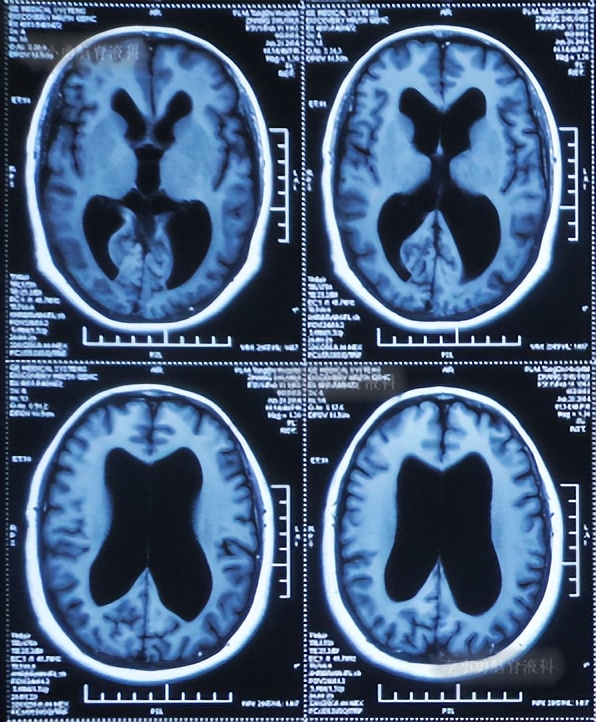

患者2014年6月20日出现持续头晕的症状,不能自行缓解,于2014年6月24日和6月26日分别就诊于甘肃省平凉县某医院和陕西省西安某医院,进行了头颅MRI和头颅CT示脑室扩张,脑积水( 图-1 、 图-2 )。

图-1: 2014年6月24日头颅MRI

图-2: 2014年6月26日头颅CT

为治疗脑积水,于头晕发病8天后即2014年6月28日,就诊于陕西省西安某三甲医院神经外科,当天查头颅MRI:脑积水( 图-3 )。

图-3: 2014年6月28日头颅MRI